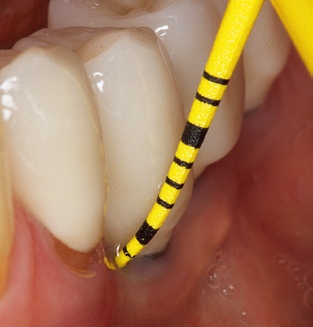

Das aktuelle Arbeitskonzept für die UPT

Die Aktualisierung der Anamnese stellt im Rahmen der UPT eine zentrale Maßnahme dar, sie sollte mindestens einmal jährlich erfolgen. Sie dient dazu, mögliche neue Risikofaktoren zu erkennen und zu dokumentieren. Vor allem dann, wenn ein Patient langjährig betreut wird, ist es wichtig, zu erfahren, ob sich patientenspezifische und allgemeinmedizinische Risikofaktoren verändert haben. Hier sollte an erster Stelle an ein erhöhtes Risiko durch Diabetes gedacht werden, aber auch andere allgemeinmedizinische Erkrankungen (kardiovaskuläre Erkrankungen und Neoplasien) können aufgrund der erfolgten Therapien und der notwendigen Medikamenteneinnahme zu einem veränderten Risikoprofil führen. Das Update der Anamnese ist also auch im Rahmen der UPT sehr wichtig, um gegebenenfalls aufgrund eines veränderten Risikoprofils eine Veränderung des Behandlungsintervalls zu veranlassen. Im nächsten Schritt ist es wichtig, der Diagnostik besondere Aufmerksamkeit zu schenken. Die Instrumentation ist zwar ein zentraler Bestandteil der UPT, in keinem Fall sollte sie aber Bestandsaufnahme und Dokumentation verdrängen. Für die Diagnose ist dabei der parodontale Befund unerlässlich, eine Zunahme der Sondierungstiefen und eine Erhöhung des BOPIndex sind zentrale Indikatoren für eine Progression parodontaler und periimplantärer Erkrankungen. Zum Erheben der benötigten Daten darf daher nicht davor zurückgeschreckt werden, auch Implantate zu sondieren. Dabei ist es wichtig, dass hierfür millimeterskalierte PARSonden verwendet werden. Für die Sondierungsbefunde an natürlichen Zähnen haben sich seit Jahrzehnten metallische Sonden bewährt. Bei Implantaten ist die Herausforderung für das Erheben korrekter und reproduzierbarer Sondierungsbefunde größer. Da es durch die Diskrepanz von Implantatdurchmesser und Kontur der Suprakonstruktion regelmäßig zu einer Überkonturierung der Suprastruktur kommt, sind für Sondierungen an Implantaten flexible, aber dennoch millimeterskalierte Son den sehr sinnvoll (z. B. Colorvue Kit PCV11KIT6, HuFriedy; Abb. 4).